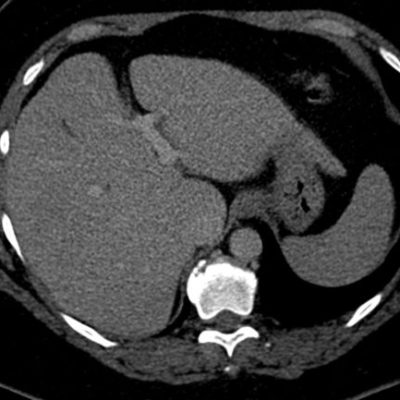

Independiente de su patrón de presentación, no condicionan cambios del parénquima luego de la administración de contraste endovenoso, no obstante igualmente se utiliza el gadolinio como medio de contraste para descartar otras entidades que puedan simular esta patología. La TC no suele aportar datos concluyentes cuando los focos de esteatosis son de pequeño tamaño y de bajo contenido graso, no logrando una adecuada diferenciación en su atenuación.7-8 (fig. 14)